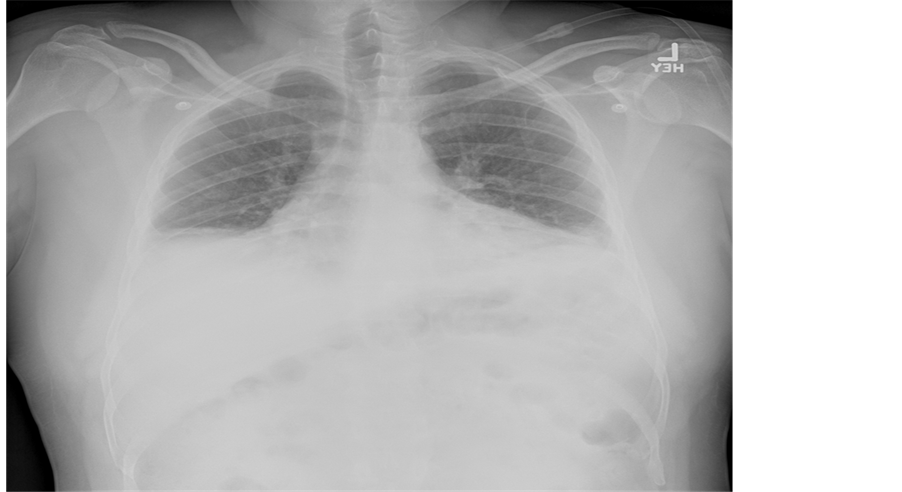

In addition to the increased work of breathing, his pulmonary exam was remarkable for bibasilar crackles. An electrocardiogram showed normal sinus rhythm with normal axis and intervals. Basic chemistry labs including a cardiac panel were with normal values save a serum creatinine of 1.22 mg/dL. Inflammatory markers were expectedly elevated with a sedimentation rate of 31 mm/h and a C-reactive protein value of 33 mg/L. A complete blood count with differential was normal. An influenza panel was negative for influenza A and B (later verified by antigen testing). An anterior chest ray revealed hypoinflated lungs with bibasilar parenchymal consolidation and associated bilateral pleural effusions (Figure 1) which were confirmed by a lateral decubitus image (Figure 2). Note, the presence of an effusion is evident by increased opacification of the compressed left lung with concomitant aeration of the right lung.

Figure 1. The figure is an erect anterior chest x-ray of the patient showing bilateral pleural effusions and lung opacification. Also noted is hypo aerated lung fields with costophrenic blunting.